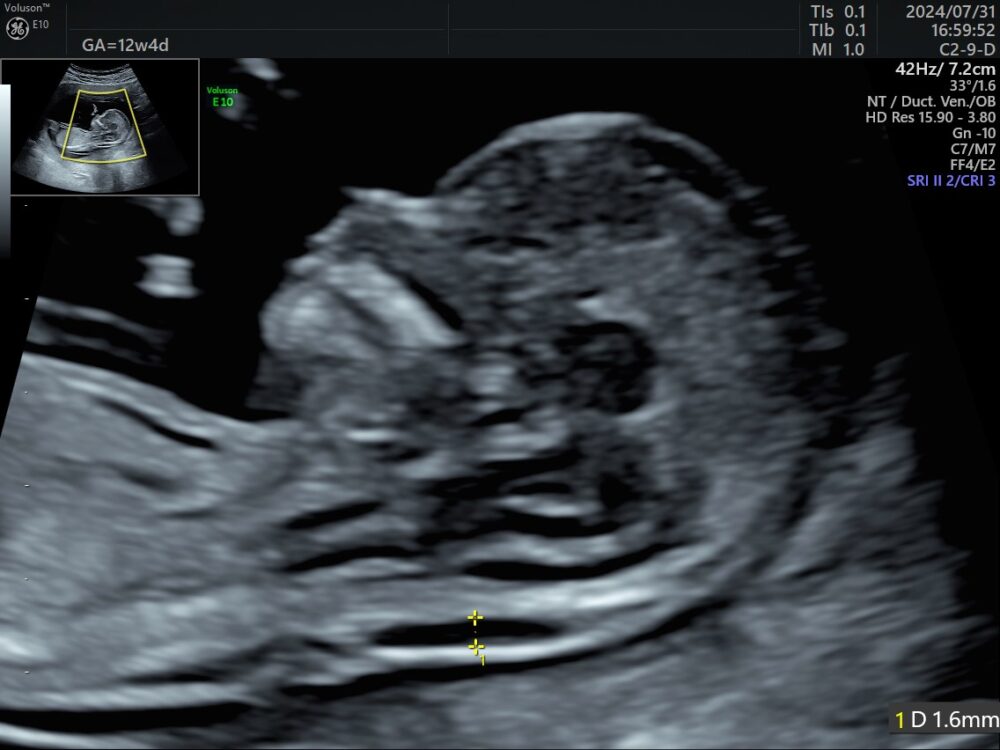

① 胎児ドック・初期精密超音波検査(妊娠12〜13週)

胎児ドック・初期精密超音波検査(妊娠12〜13週)当院では、胎児精密超音波検査(胎児ドック)に力を入れております。超音波を使用して、胎児・胎盤・臍帯などの週数に応じた全身のチェック項目を観察し、大きな形態異常がないかしっかりと丁寧に観察します。超音波では染色体を見ることはできませんが、赤ちゃんの疾患や奇形は染色体疾患がなくても3-5%の確率で起こると言われており、超音波による検査は非常に大切です。

この検査は、検査を行う医師の経験や技量が非常に重要になります。当院では、産婦人科専門医・指導医・周産期専門医だけでなく、英国Fetal Medicine Foundation(FMF)認定のエコーライセンスを保有している副院長がこの検査を行いますので、どうぞご安心ください。

初期精密超音波に含まれるNT(赤ちゃんの首のむくみ)は、実は正確な測定は非常に難しく、細かい規定があります。

当院ではイギリスのFetal Medicine Foundationのライセンスを取得した、正確な計測ができる副院長の高橋雅也医師が、NTを含めた胎児の全身のチェック項目を丁寧に観察します。